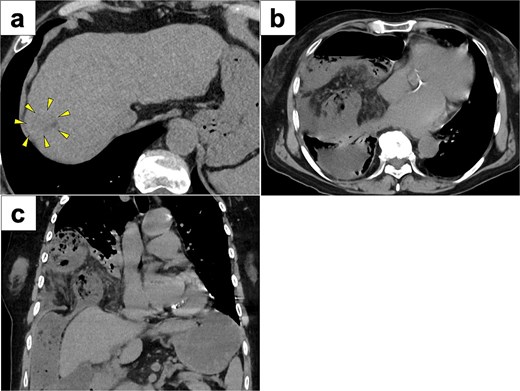

A 77-year-old women presented to the emergency department with sudden-onset of abdominal pain. Her medical history included alcoholic liver cirrhosis and HCC in liver Segment 8, previously treated with ultrasound-guided RFA 8 months prior. The HCC was a 20-mm lesion located in the subcapsular portion of hepatic Segment 8 (Fig. 1a). Her vital signs were unremarkable. On physical examination, she had marked tenderness in the right upper quadrant. Laboratory tests revealed normal inflammatory markers: white blood cell count of 5330/μl and C-reactive protein 0.1 mg/dl. Regarding hepatic function, she was classified as Child-Pugh score 5, with total bilirubin 1.6 mg/dl, albumin 3.9 g/dl and prothrombin time percentage 77.5%. Computed tomography (CT) imaging demonstrated transverse colon incarceration into the thoracic cavity, with mesenteric edema (Fig. 1b and c). A diagnosis of intestinal incarceration due to DH was made, and emergency surgery was performed. First, a 12-mm trocar was placed at the umbilicus for the scope. Additionally, we placed a 12-mm trocar in the left upper abdomen, a 5-mm trocar in the right upper abdomen, and a 5-mm trocar in the right flank for support (Fig. 2a). Laparoscopic exploration confirmed incarceration of the hepatic flexure (Fig. 2b). The incarcerated colon was carefully reduced, and indocyanine green (ICG) perfusion imaging confirmed adequate blood flow, avoiding the need for intestinal resection. A 50 × 50 mm diaphragmatic defect was identified and repaired using barbed non-absorbable sutures (1-0 V-Loc; Medtronic, Covidien) (Fig. 2c and d). The operative time was 95 min with minimal blood loss. The postoperative course was uneventful, and the patient resumed oral intake on postoperative day 1 and was discharged on postoperative day 8.

CT images of preoperative examinations. (a) Pre-RFA CT showing that HCC was a 20-mm lesion located in the subcapsular portion of hepatic Segment 8 (arrow). (b and c) Axial and coronal abdominal CT showing incarceration of the transverse colon into the thoracic cavity.